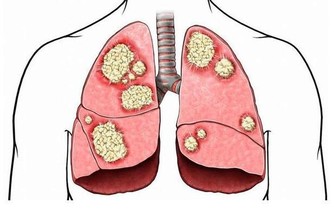

眾所周知,一旦尿酸高了,會引發全身性疾病,首當其衝的就是關節疾病,對於腎臟、血管等都會有不同程度的損害,還會影響血糖引發糖尿病等等。